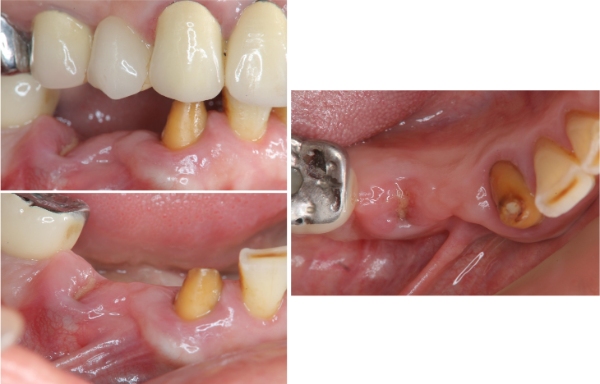

治療前,右下顎殘根

治療前,口內殘根與缺牙